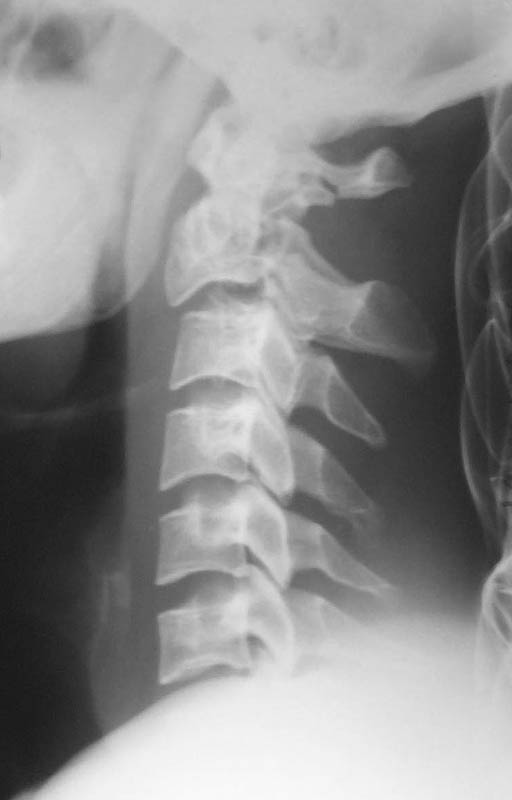

From: DR T I GEORGE

The cervical spine x-ray done on traction in neutral, extension and flexion. Images attached. Request comments.

txn extension

txn neutral

txn flexion

The skull traction is being continued. My colleague, Dr K P Ramkumar, Chief of our Spine unit, said that the the cervical injury belongs to Levine type II and most probably it will be conservative management only. However he wants to repeat the x-ray on traction after a few days and do also a dynamic flexion and extension view. The need for surgical intervention will be decided after this. He also feels that patient has a subjective numbness of finger tips and mild grip weakness. According to him this indicates that the spinal cord had minimal trauma.